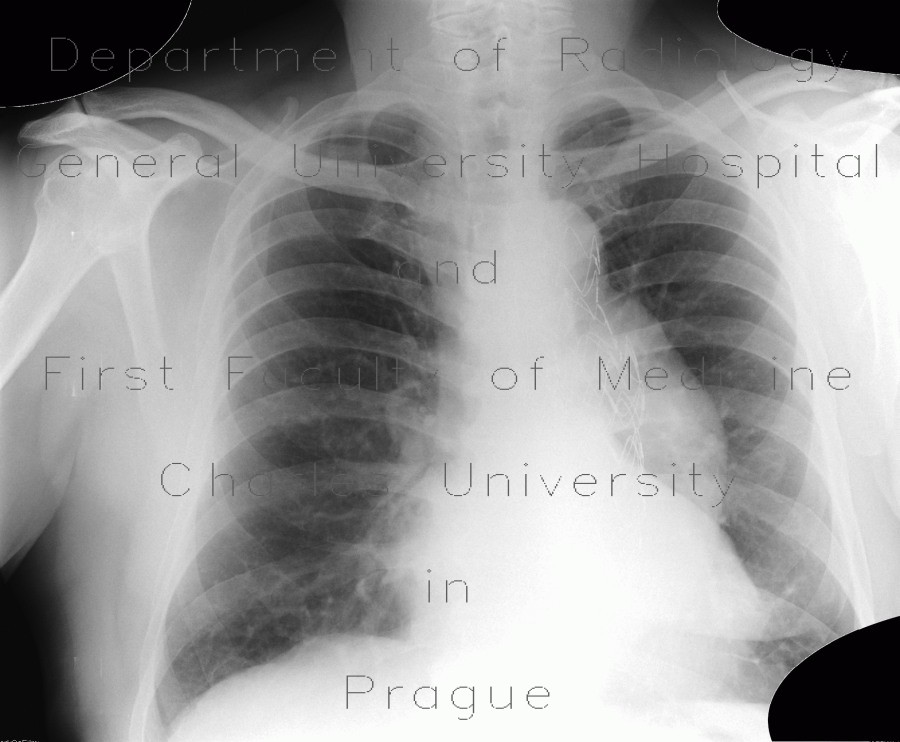

Thoracoabdominal Aortic Aneurysm Hernan A. Bazan, Nicholas J. Morrissey, Chest X-ray (Fig. 5.1) was remarkable for a tortuous aorta, which had calcification within the wall and appeared dilated. as the ratio of abdominal aortic aneurysm (AAA). ... Fetch Full Source